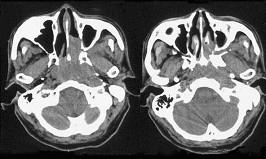

问题 男,64岁,间断性流鼻血1年余,近1个月加重,CT如图所示,最可能的诊断为()

选项 A.鼻咽部腺样体增生 B.鼻咽纤维血管瘤 C.鼻咽部恶性淋巴瘤 D.鼻咽部淋巴组织增生 E.鼻咽癌

答案 E